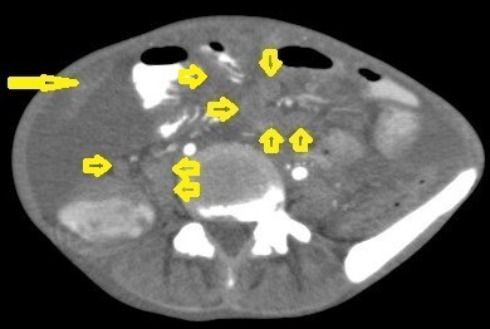

Figure 20. Tuberculous lymphadenitis in a 27-year-old women with cachexia, loss of appetite and cough. Axial abdominal CT image shows enlarged mesenteric, periaortic, and portahepatis lymph nodes (LNs), (short arrows) due to TB, which usually involves multiple groups, such as mesenteric and upper paraortic LNs. The image also shows relatively dense ascites and remarkable omental thickening forming cake-like mass (long arrow).

Figure 21. Wet peritonitis in a 16-year-old man with cachexia and loss of appetite. Selected axial abdominal images show marked relatively dense ascites and gross thickened omentum with faint enhancement of peritoneal reflections (long arrows) with multiple enlarged mesenteric and upper paraortic conglomerated lymph nodes (short arrows) with slight homogeneous enhancement.

Figure 22. Fibrotic peritonitis in a 20-year-old man with fatigue, abdominal distension, and loss of appetite. Selected axial images of abdominal CT show remarkable omental thickening, forming cake-like masses (arrows) with faint enhancement and mild smooth thickening of peritoneal reflections associated with mild-to-moderate dense ascites and several low-attenuation mesenteric lymph nodes that are challenging to be distinguished from small bowel loops.